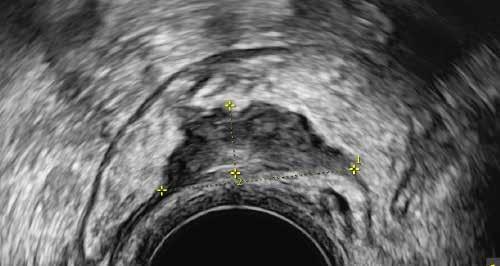

Infolge dauert es im Schnitt sieben Jahre, bis die korrekte Diagnose gestellt wird. Um auch bei aty pischen Symptomen an Endometriose zu den ken, braucht es Erfahrung. Die Anamnese hat einen sehr hohen Stellenwert in der Diagnostik und wird sehr umfassend erhoben. Ist die Ver dachtsdiagnose gestellt, muss eine Einschätzung der Ausbreitung erfolgen. Auch die gynäkologi sche Untersuchung geht über die eines RoutineCheck-Ups deutlich hinaus. Einen zunehmenden Stellenwert hat die Sonographie bekommen. Am Endometriosezentrum arbeiten wir mit moderns ten Ultraschallgeräten. Damit sind wir in der Lage, auch kleinste Endometrioseläsionen aufzudecken. Die Sonographie ist, sofern sie von EndometrioseExperten durchgeführt wird, gleich sensitiv und spezifisch wie eine MRI-Untersuchung.

Endometriose-Herde im Darm

In diesem Fall waren die Endometriose-Herde nur auf dem Ultraschall erkennbar, im MRI hin gegen nicht.

Ultraschall Foto von der Operation Makrofoto Pathologie

Unser aus zwei Gynäkologinnen und drei Gynäko logen bestehendes Endometriose-Team ist aus gebildet, im optimalen Fall die kleinen, einige Mil limeter grossen Herde sonographisch darstellen zu können. Bei der systematischen Untersuchung werden zudem nicht nur der Uterus und die Ova rien, sondern die komplette Umgebung der inne ren Geschlechtsorgane im kleinen Becken darge stellt. Dies beinhaltet die komplette Darstellung der Ligamenta sacrouterina, der Tuben, Urethra, Blase, Ureteren und die Rektum-, Sigmawand. Die Beurteilung der Darmwand hat eine beson dere Bedeutung, da bei vermutetem Darmbefall die präoperative Vorbereitung interdisziplinär mit den chirurgischen Kollegen stattfinden muss. Bei bestimmten Fragestellungen (z. B. Cavumform, Junktionalzone) kommt die 3D-Sonographie zum Einsatz. Bei der bimanuellen Untersuchung wird die Muskulatur im kleinen Becken beurteilt, um eine mögliche myofasziale Schmerzkomponen te auszuschliessen. Zudem wird die Reprodu zierbarkeit der Schmerzen überprüft. Wenn die anamnestisch angegebenen Schmerzen an be stimmten Lokalisationen ausgelöst werden kön nen, wird die Therapie-, und Operationsplanung deutlich einfacher.

Befund am Ureter

Kaudale Ureter-Dilatation bei kleinem Endometrioseherd an der UreterA. uterina Kreuzung